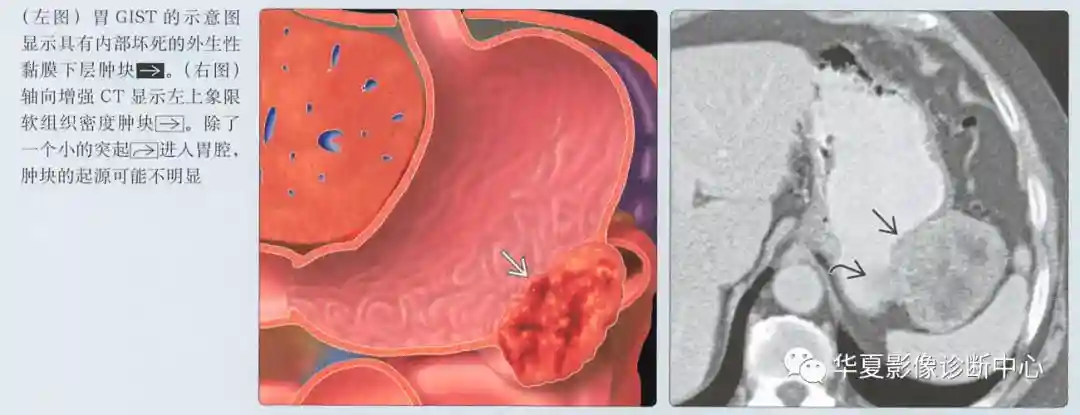

最佳诊断线索

边界光整,黏膜下层肿块向消化道外生性生长

通常是外生的,可能有囊性成分

动脉期图像呈低或高血供,边界清楚的黏膜下肿块;溃疡和坏死是常见的

具有大的腔内成分的肿瘤可能类似原发性胃癌